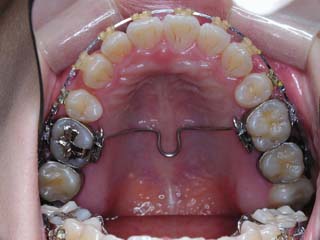

主訴:上の歯が出ている

診断名:顎関節症、下顎左右5欠損を伴う骨格性上顎前突

年齢:35歳

使用した主な装置名:TPB、マルチブラケット装置

抜歯/非抜歯および抜歯部位:非抜歯

治療期間:動的処置2年、経過観察3年

費用の目安:保険適応 自己負担金として30~50万

リスク、副作用:外科手術によるリスク、マルチブラケット治療に伴う歯根吸収など偶発症が発生するリスクがある。

強い骨格性の上顎前突が見られます。しばしば、口腔内所見では骨格のズレを歯の補償的な傾斜などでカムフラージュさせているため、あまり大したことのないズレにしか見えない事があります。また、上顎前突の場合は、下顎が関節の位置で知らず知らずのうちに前方へ大きく偏位させて噛んでいる事が多いです。このような場合は、咬合器に装着してみて初めて、治療方針が見えてくるかもしれません。どのような不正咬合であれ、大きなズレに対しては、外科的に骨のズレを改善する治療が理にかなっています。前後のズレ、垂直のズレと条件が重なってきた場合、より外科矯正での改善が望ましいでしょう。

一般的な外科矯正治療の流れは、術前矯正・外科矯正・術後矯正・保定治療と移行します。術後矯正では、手術後に僅かに見られる後戻りに対する処置や、刻々と変化する額関節の環境に対応して調節を続けます。特に大きな問題が無ければ6か月程度で保定治療に移行します。